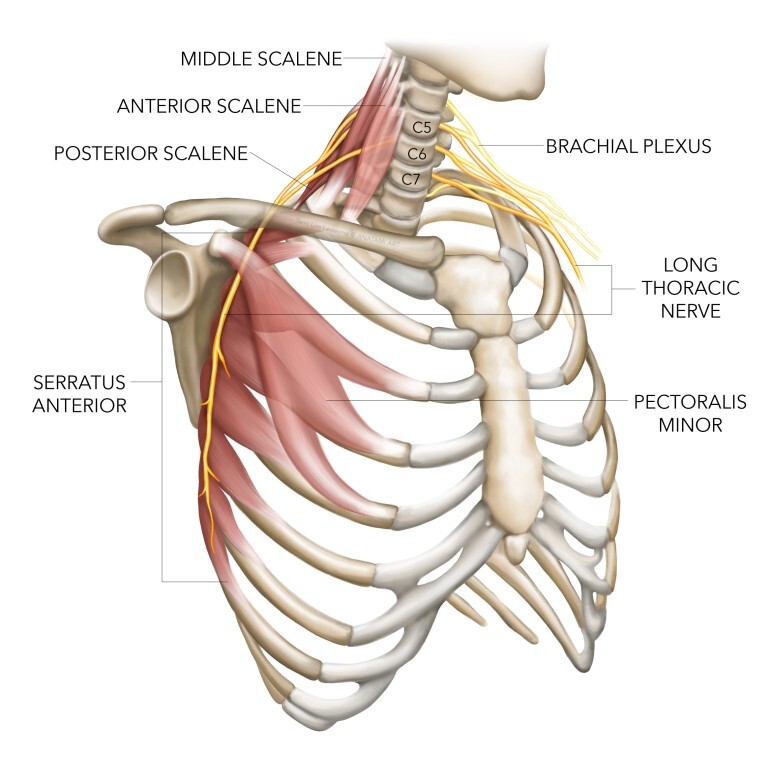

가장 흔한 이유로서 견갑골의 안정화를 도와주는 근육들의 문제가 있을 때 발생됩니다. 이러한 역할을 도와주는 근육들은 상부승모근, 전거근, 하부승모근, 능형근, 견갑거근, 소흉근이 작용해줍니다.

이중에서 전거근과, 하부 승모근은 견갑근에 내측끝에 위치해서 상방회전하면서 팔의 외전동작에서 중요한 역할을 합니다.

▶ 신경문제로 인한 근육이상

종종 신경의 문제가 원인이 될 수 있는데 대표적으로 긴가슴신경(장흉신경, Long thoracic nerve) 또는 척수부신경(Spinal accessory nerve), 등쪽어깨신경(Dorsal scapular nerve), 등의 손상으로 인한 전거근이나 승모근, 능형근의 문제가 생길 수 있습니다. 이 경우는 흔하지는 않습니다.

특히 오훼돌기(Coracoid process)에 붙는 소흉근(Pectoralis minor), 이두근건 장두(Short head Of biceps)의 단축은 견갑골을 위에서 아래로, 앞으로 잡아당기게 되면서 견갑골의 앞쪽 기울임(Anterior tilt)을 유발하며 문제를 일으킬 수 있습니다. 따라서 충격파 치료 시 치료포인트가 이두근의 원위부인 팔꿈치 오목 상부인 이유가 됩니다.

전거근과 승모근은 견갑골의 안정화에 매우 중요한 근육입니다. 특히 이 근육들은 상지 운동을 할 때 함께 작용하고, 특히 머리쪽으로 손을 올리는 동작들(Overhead position)에서 중요하게 작용합니다.[47][48] [49]

또한 운동이상증을 일으키는 주요 근육이기 때문에 [16] 재활 시 중요합니다.

안정적인 표면에서의 푸쉬업은 전거근(=앞톱니근)의 근력을 증가시키고, Red Cord sling으로 전반적인 근력을 향상시켜줄 수 있습니다. 불안정한 표면에서 푸쉬업을 하면 승모근 활성화가 증가하는 반면 전거근 활성화는 감소합니다.

척수부신경(Spinal accessory nerve)의 문제나 장흉신경(long thoracic nerve)이 직접손상인 경우에 마비의 경우에, 심한경우에는 수술적으로 신경을 이어줄 수도 있지만, 심하지않은 손상의 경우에 장흉신경은 대부분 2년내 회복이 되므로 보존치료를 해볼 수 있습니다.